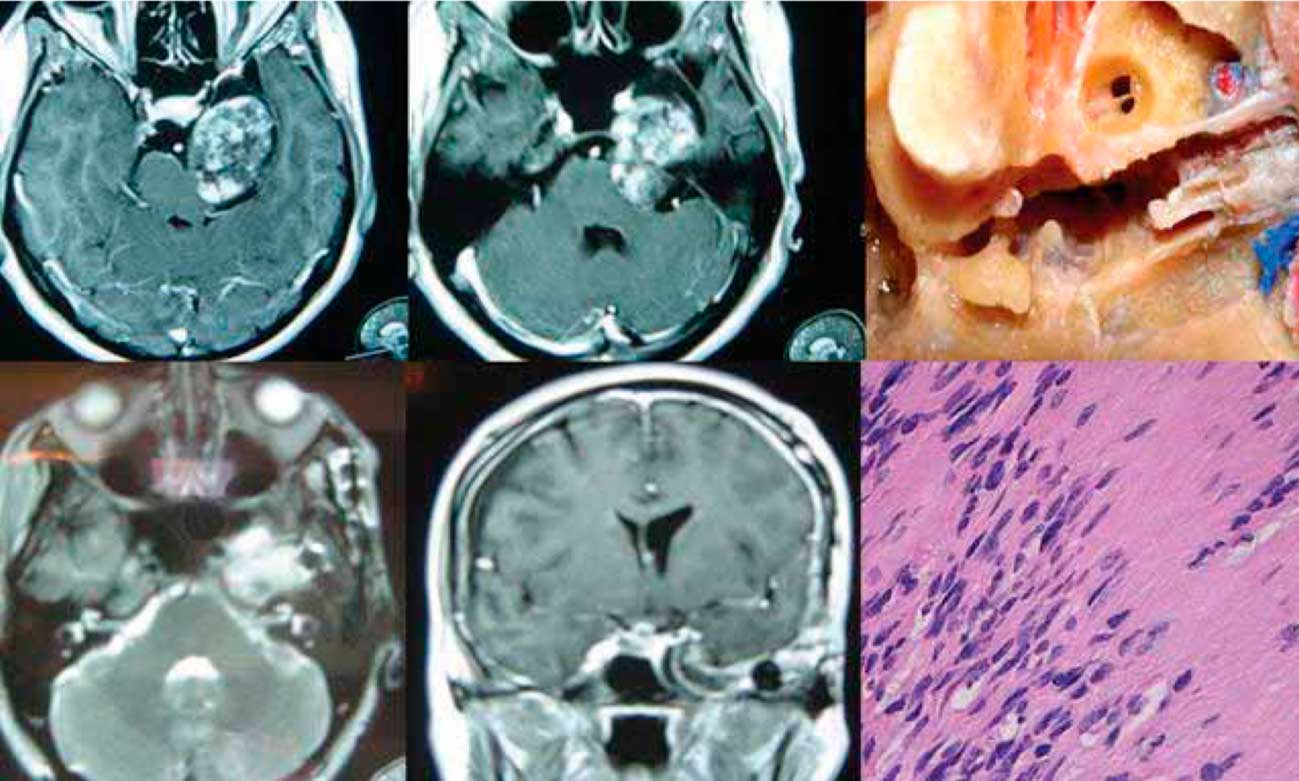

Cirurgia da base do crânio: uma desafiadora especialidade da medicina moderna

A cirurgia da base do crânio emerge como uma especialidade da medicina moderna. Seu principal objetivo é tratar lesões, principalmente tumores (neurinomas, adenomas e meningeomas), situados em complexa topografia anatômica e que, há duas décadas, eram considerados inoperáveis. O objetivo desta revisão é fornecer aos médicos generalistas uma visão dos aspectos conceituais, históricos, patológicos, epidemiológicos, clínicos e terapêuticos em cirurgia da base do crânio.

Cirurgia Da Base Do Cranio – Uma Desafiadora Especialidade Da Medicina Moderna